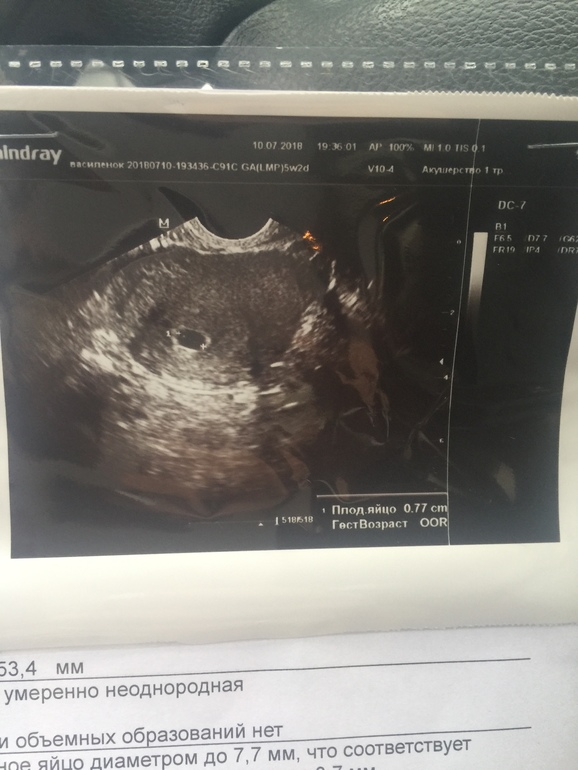

Первое фото , ничего интересного, просто плодное яйцо в матке , это 10 день задержки. А вот второе фото - на 24 день задержки - уже и малышика хорошо видно и сердечко слышаться ) Так что лучше дождаться хотя бы 20 дней и уже идти смотреть все в целом :)